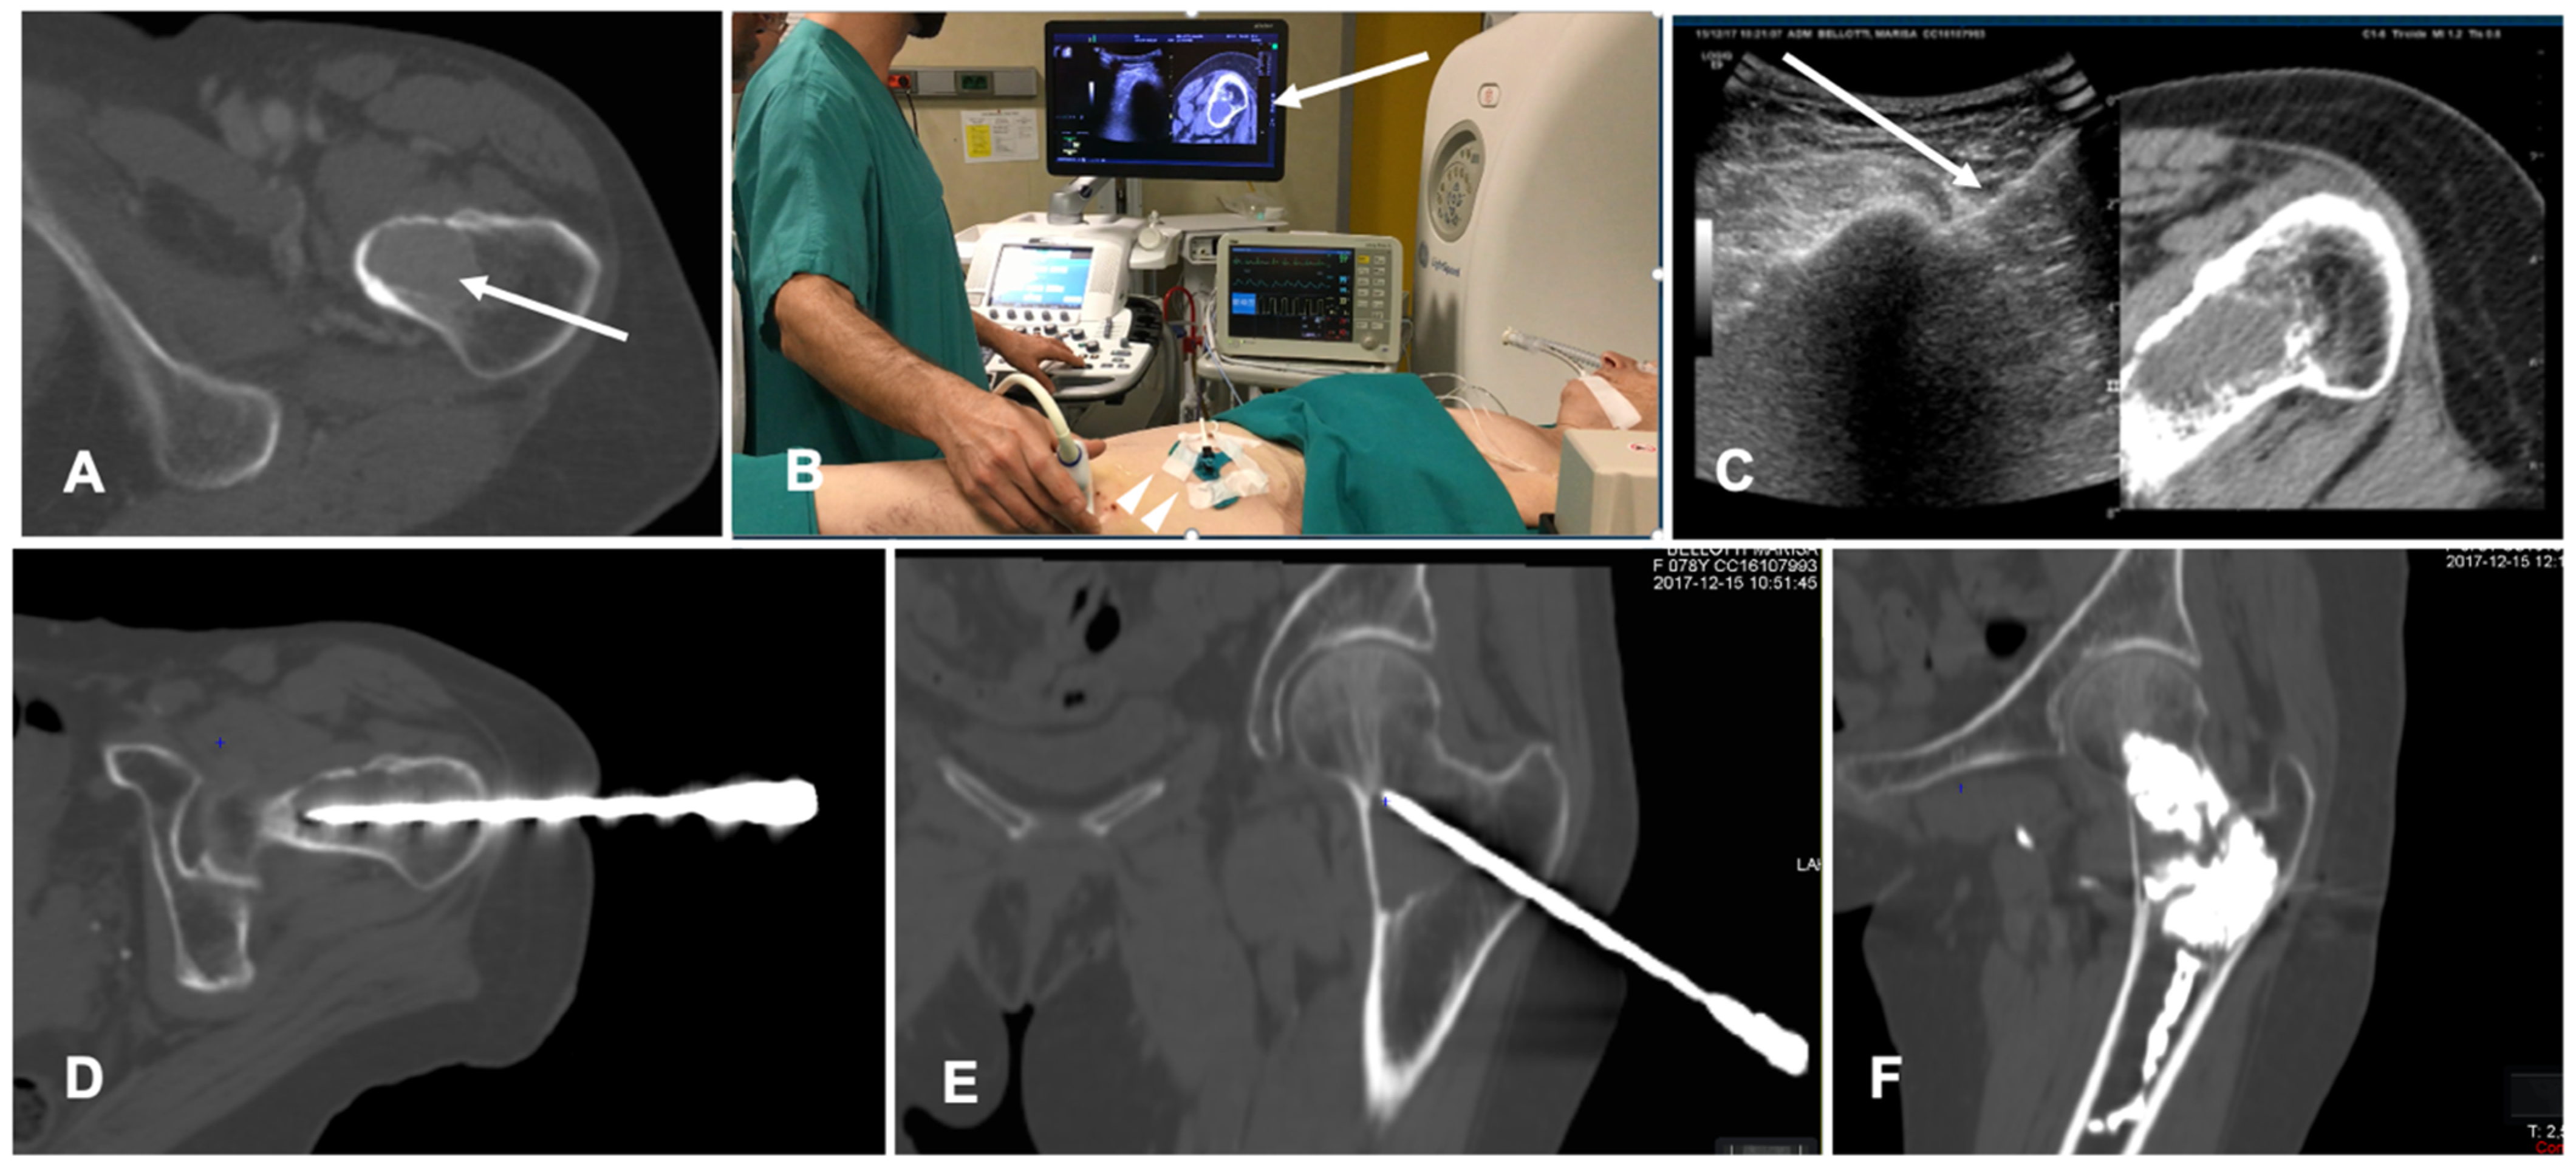

FI technique is recently being applied to lung procedures since software algorithms were developed to register the intraprocedural anatomic imaging with preprocedural PET/CT data. Some studies reported the experience of fusion PET/CT-CBCT studying it in guiding percutaneous biopsy of lung lesions compared with CBCT guidance [40,41,42]. PET/CT-CBCT-guided is feasible and safe as CBCT-guided biopsy with a lower number of non-diagnostic samples and false-negative cases, with evidence of metabolic information provided by a prior PET/CT and a better quality of the samples obtained with FI guidance [40]. Systems that allow to guide a virtual needle on a pre-acquired lung CT have been implemented to reduce the number of CT acquisition required in lung procedures and to improve the non-axial approach in CT guided lung ablations. A case of a lung nodule treated with microwave ablation is shown in Figure 4.

FI has also been tested in spine procedures. CT/US FI was demonstrated to be feasible and safe in guided bone biopsy of spinal lesions; this technique allows for continuous needle monitoring and image acquisition, avoiding the need for repeated CT scans and decreasing the number of CT passes throughout the procedure with shorter lead times compared to standard CT guidance [47]. A case of a bone ablation performed with the assistance of FI is shown in Figure 5.

Figure 5. Case of a patient with a breast cancer femoral neck metastasis treated with cryoablation. (A) Axial view of the preoperative unenhanced Computed Tomography (CT) showing a lytic ovoid femoral neck lesion (white arrow); (B) Intraoperative setting for fusion imaging (FI): ultrasound (US) system with automatic image registration of fused images with previously acquired CT volume data sets (white arrow), a disposable locating device and sensor (white arrowheads) and electromagnetic generator (white asterisk). (C) Live FI with CT multiplanar reconstruction (right side) and US (left side). With combined CT-US imaging the needle (white arrow) can be oriented along the major axis of the bone lesion regardless the acoustic barrier. (D,E) A paraxial view and a coronal view along the needle length of the intraoperative CT confirming correct positioning into the lesion. (F) Final control CT on coronal plane after cryoablation and cementoplasty.